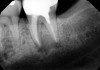

The patient stated that a previous root canal had been performed on tooth No. 18 many years ago, but he had no memory of the exact date or the name of the dentist who provided the treatment. The referring dentist had no records or preoperative radiographs of tooth No. 18 from before the initial endodontic treatment. A limited FOV CBCT scan of the tooth was taken, and a radiolucency was observed on the mesial and distal roots (Figure 4). The pretreatment pulpal diagnosis was "previously treated," and the periradicular diagnosis was symptomatic apical periodontitis.

The clinician determined that the treatment options were conventional endodontic retreatment or endodontic surgery, which would involve resectioning of the mesial and distal roots, preparation of the root ends, and placement of a bioceramic root-end filling. With regard to restorative evaluation, the existing crown on tooth No. 18 was deemed to be within normal limits. Although the periapical radiograph (Figure 3) showed a radiolucent line around the distal portion of the crown, the marginal integrity was determined to be clinically acceptable. The CBCT demonstrated that the inferior alveolar nerve canal was close in proximity to the mesial and distal roots of tooth No. 18. Also, clinically the surgical access around tooth No. 18 was limited for root-end resection endodontic surgery. The axial CBCT view showed that the current canal obturation was within normal limits (Figure 5).

CBCT sagittal view (lingual view exposure) of tooth N o. 18 revealed mesial

and distal root periapical radiolucency.

Fig 4.

CBCT axial view of tooth

No. 18 revealed canal obturation within normal limits.

Fig 5.